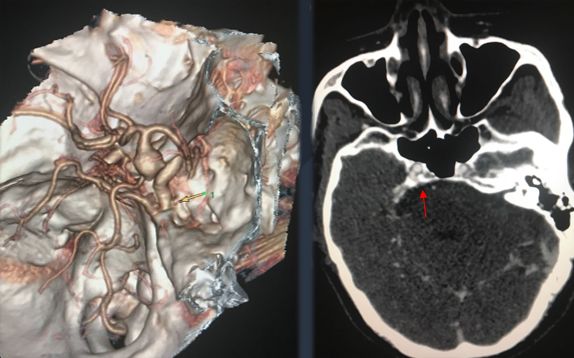

孟浩医师:胚胎性大脑后动脉起始处动脉瘤

574x358 - 39KB - JPEG